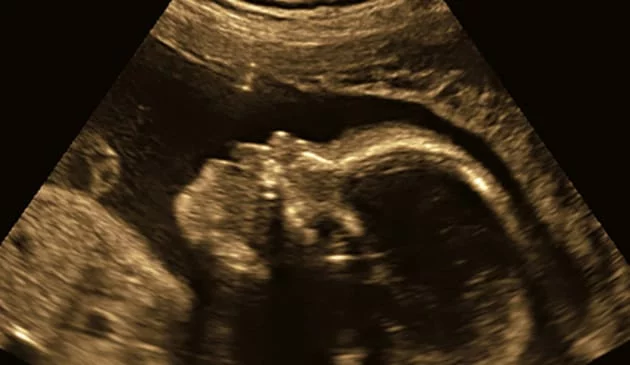

Ultrasound of a baby

At what scan do you find out the baby's sex?

Your baby's sex is determined at the moment of conception, when the sperm meets the egg and the baby gets its 23 chromosomes from each parent. The genitals start to develop at around 11 weeks but you won't be able to find out the baby's sex at your 12 week scan, as things won't be sufficiently developed by then.

Instead, it will be another several weeks before your doctor can determine your baby's sex from an ultrasound. Your 20 week scan is the big one when all will be revealed (although some couples still like to sustain the mystery all the way to the baby's birth).

• Skull theory. Look at the ultrasound. Does your baby have a square jaw? Then you’re probably have a boy. Rounded jaw? Well, then obviously it’s a girl.

Entertaining as all this speculation might be, the only way to know what gender your baby will be or, how many babies you’re having, is to see the ultrasound.